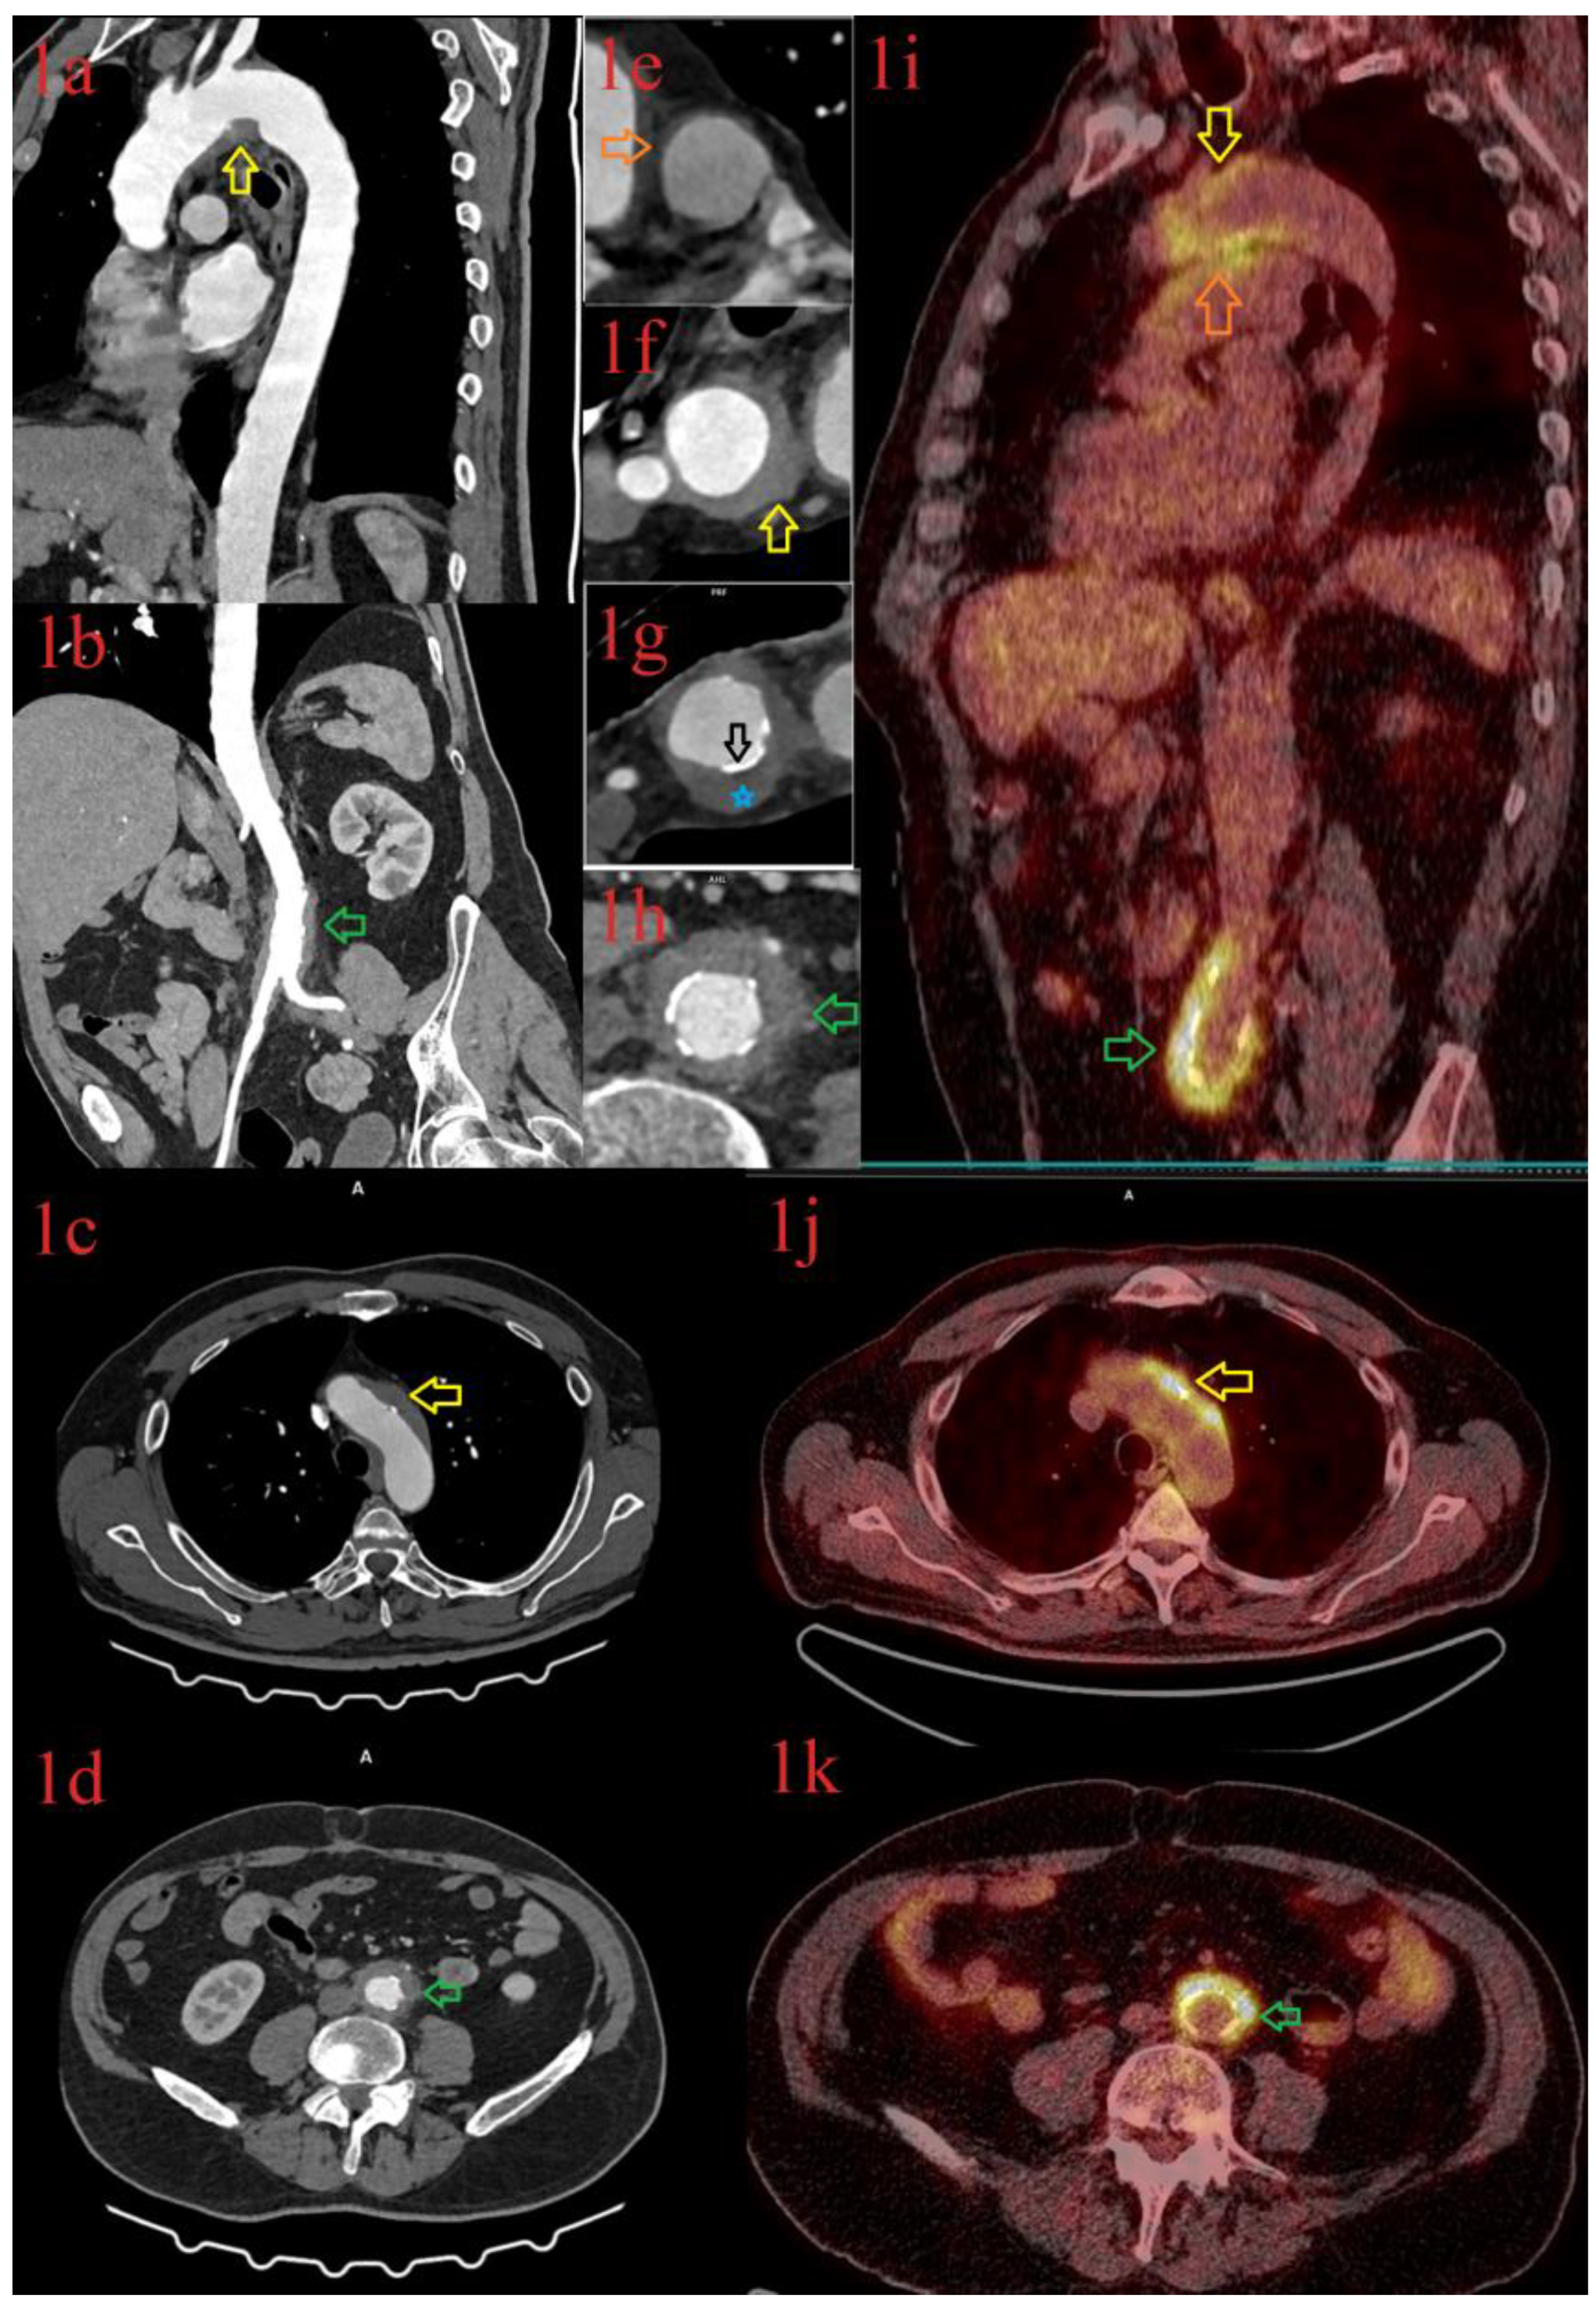

3.1.1. Patient 1

3.1.2. Patient 2

3.1.3. Patient 3